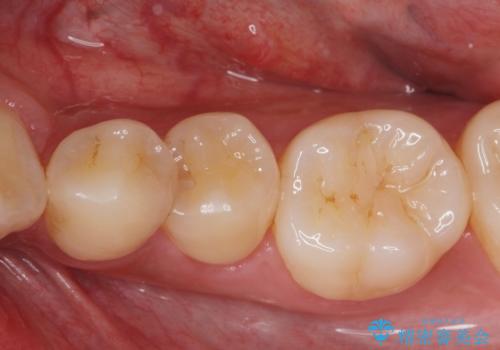

[e-maxインレー] 矯正治療前の虫歯治療

- 矯正治療前の患者様です。

う蝕があったのでe-maxインレーにて治療しました。

- e-maxインレー 7.7万円 費用は治療当時の料金となります

う蝕があるままで矯正を始めてしまうと矯正治療中にう蝕が悪化する可能性があります。矯正治療を行う前はう蝕や歯周病がある場合にはしっかり治療を行なってから矯正治療がスタートします。

![[e-maxインレー] 矯正治療前の虫歯治療の治療前](https://seimitsushinbi.jp/wp/wp-content/uploads/2023/08/IMG_1023-1-500x350.jpg?v=1691812306)